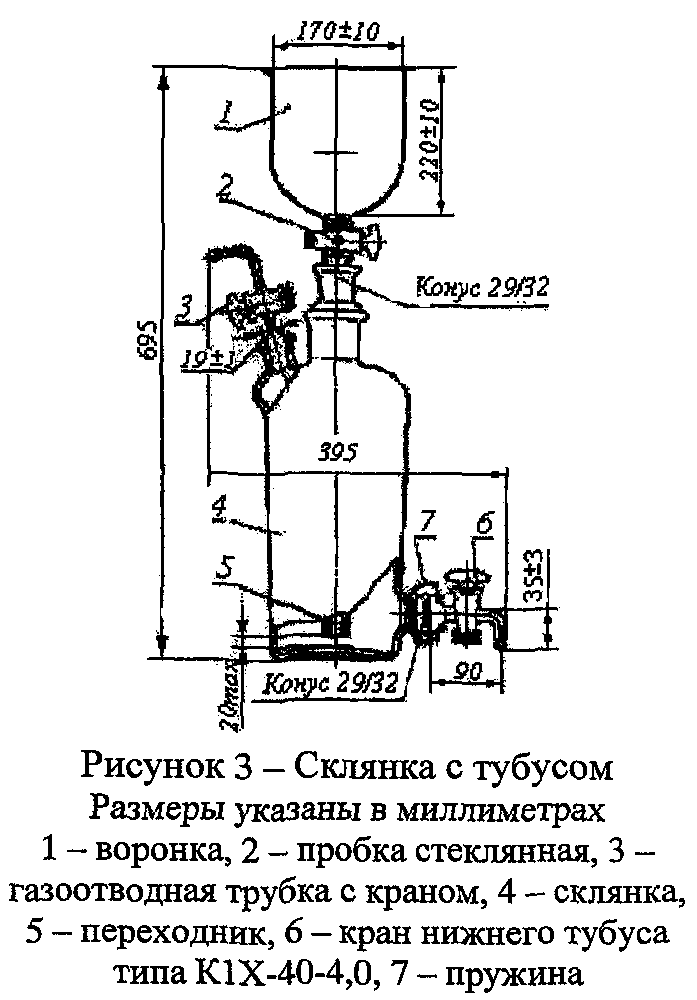

Объём кислорода, пропущенный через поглотительный раствор, измеряют с помощью склянки с тубусом (рис. 3) или прибора для отбора проб газа (рис. 4), присоединенного к короткой трубке склянки (рис. 1 или 2) на выходе газа.